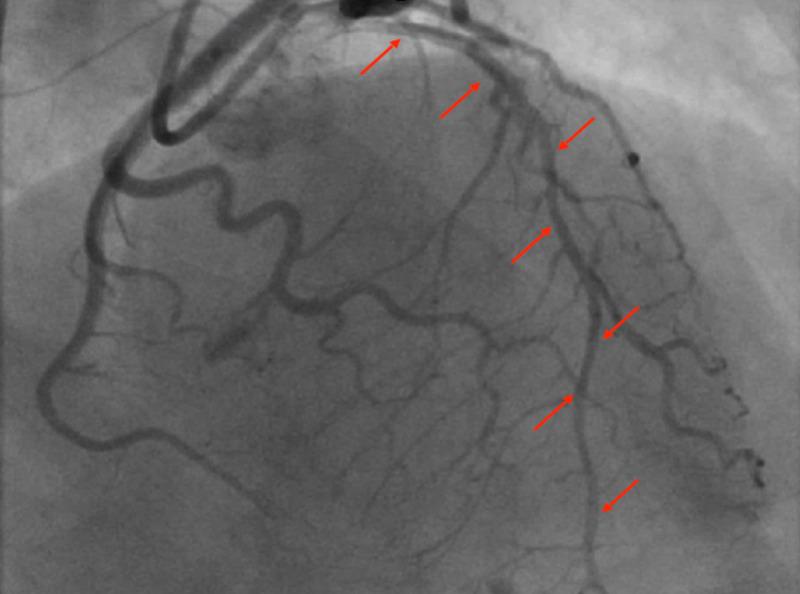

自发性冠状动脉夹层:年轻男性ST段抬高型心肌梗死的罕见病因。

Spontaneous Coronary Artery Dissection: An Unusual Cause of ST-Elevation Myocardial Infarction in Young Males.

Spontaneous coronary artery dissection (SCAD) is a non-traumatic, non-iatrogenic, and non-atherosclerotic coronary artery disorder that manifests clinically as an acute coronary syndrome (ACS), arrhythmia, or sudden cardiac death (SCD). It is a rare cause of ACS (1.7-4%) and SCD (0.5%), more commonly in women than men. It is rarely reported in males. We report a case of acute ST-elevation myocardial infarction (STEMI) due to SCAD in a 44-year-old healthy male.

摘要

自发性冠状动脉夹层(SCAD)是一种非创伤性、非医源性且非动脉粥样硬化性的冠状动脉疾病,临床上表现为急性冠状动脉综合征(ACS)、心律失常或心源性猝死(SCD)。它是ACS(1.7 - 4%)和SCD(0.5%)的罕见病因,女性比男性更常见。男性中鲜有报道。我们报告一例44岁健康男性因SCAD导致的急性ST段抬高型心肌梗死(STEMI)病例。